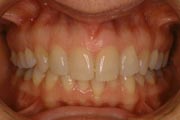

Crowding

Before